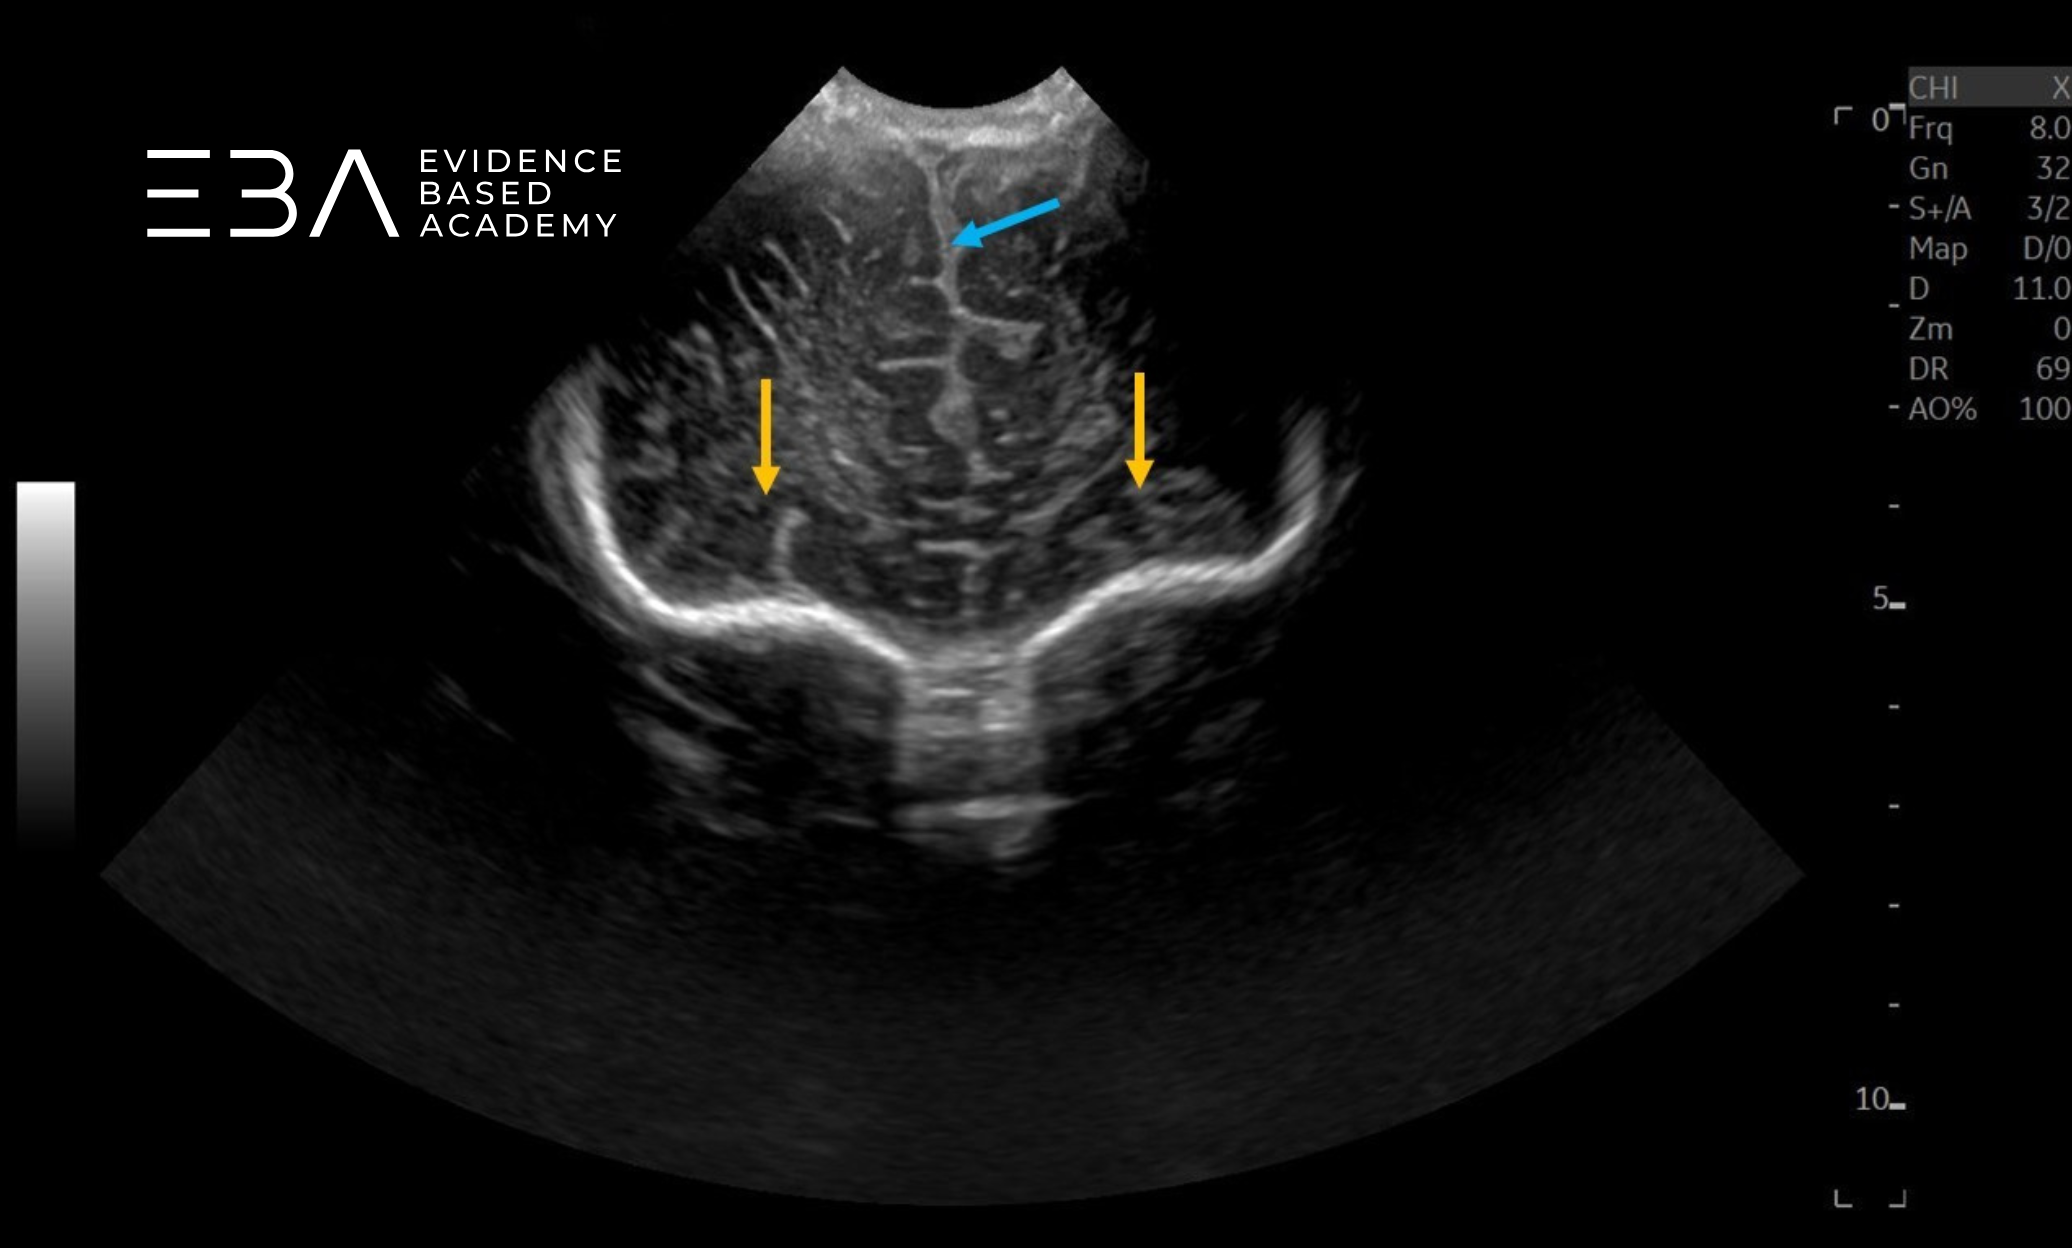

zdj. 5a

Głowica liniowa – badanie przez łuskę kości skroniowej. Konary mózgu (żółte strzałki), wodociąg mózgu (czerwona strzałka).